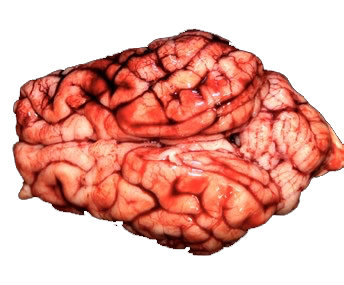

Streptococcus suis: claves diagnósticas desde la lesión hasta el laboratorio